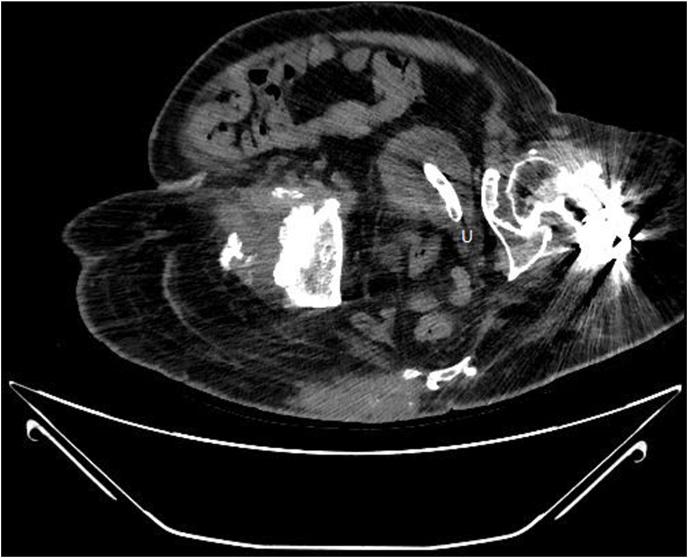

Obstruction of a ureter orifice by suprapubic catheter.

An Indwelling suprapubic catheter is an established solution for patients with meningomyelocele neurogenic bladder. We report on a case in which a routinely replaced suprapubic catheter obstructed the left ureter orifice. The catheter drainage holes were inside the distal left ureter which compromised urinary drainage from the other kidney as well. As a result, the patient suffered from acute renal failure. During his hospitalization, the catheter was replaced and re-located, and renal function rapidly improved. This case emphasizes that even procedures that have been routinely performed for decades can manifest with an unusual complications.

耻骨上留置导尿管是治疗脊髓脊膜膨出神经源性膀胱患者的一种成熟方法。我们报告了一例常规更换的耻骨上导尿管阻塞左输尿管口的病例。导尿管引流孔位于左输尿管远端内部,这也影响了对侧肾脏的尿液引流。结果,患者出现急性肾衰竭。住院期间,更换并重新放置了导尿管,肾功能迅速改善。该病例强调,即使是已常规进行数十年的操作也可能出现罕见并发症。